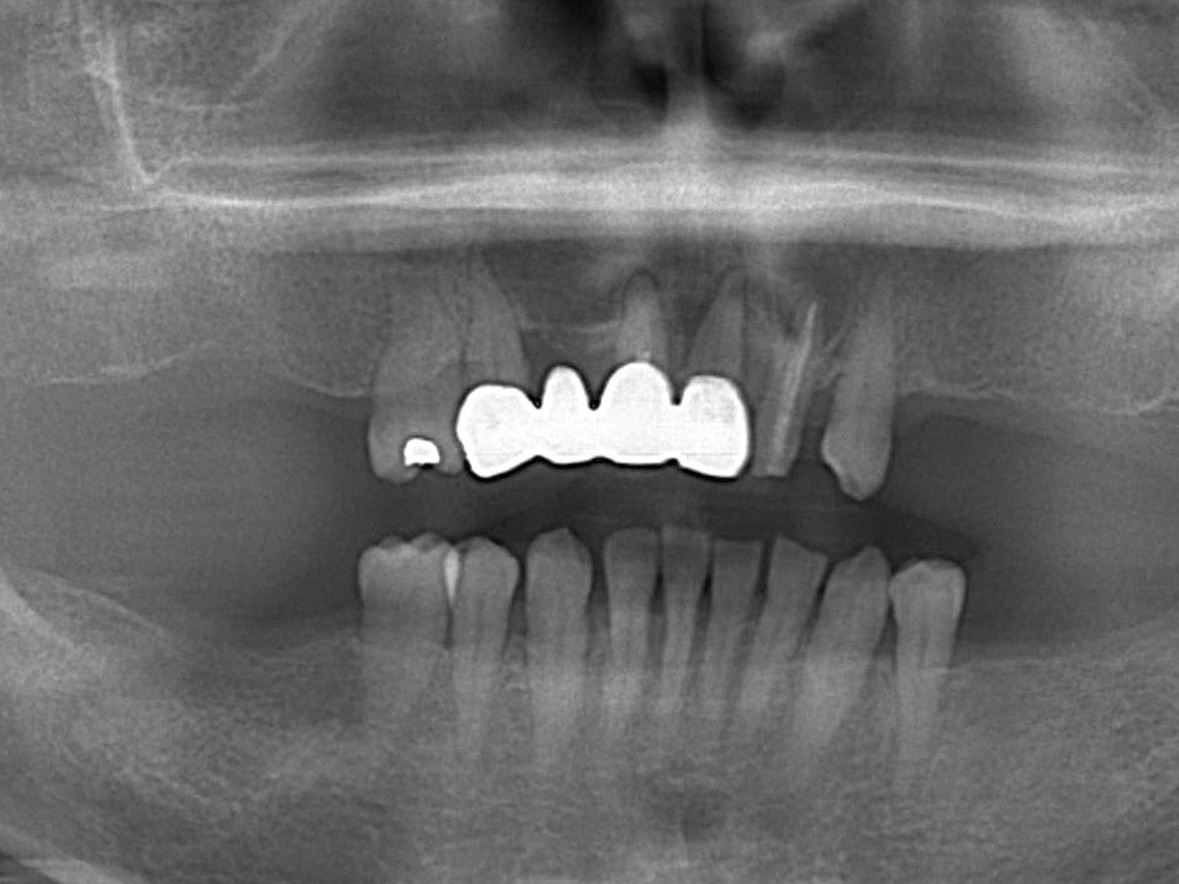

症例1

患者様の年齢 30代男性 主訴 前歯がないため噛みきれない、見た目も気になる 治療内容 前歯部インプラント治療3本

抜歯即時インプラント埋入後3ヶ月の待機期間後、ジルコニアによる上部構造装着着費用 142万円 治療期間・通院回数 5ヶ月/7回 デメリット・リスク 外科処置に伴う痛み・腫れ・出血・合併症の可能性があります。 -